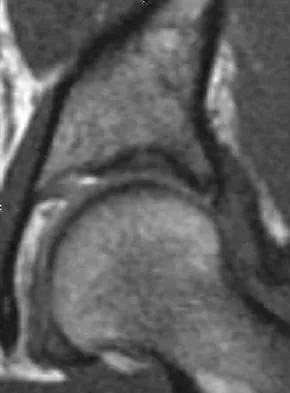

A 19-year-old man has had back pain with activity, especially running in soccer and baseball, for the past 4 months. He denies any history of trauma. Examination reveals no motor weakness or sensory changes in the lower extremities. Range of motion shows increased pain with extension and mild limitation with flexion. A sitting straight leg raising test is limited at approximately 60 degrees bilaterally by back and buttocks pain. Plain radiographs are normal. MRI scans are shown in Figures 13a through 13e. What is the most likely diagnosis?

Explanation